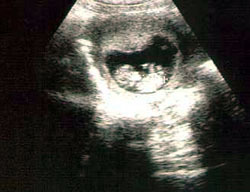

الأسبوع السابع:

ينمو الجنين في هذا الأسبوع بشكل أكبر ويصبح حجمه في حجم حبة الفول ويصبح طوله 1.25 سم. يبدو شكل وحجم الرأس أكبر عن باقي حجم الجسم بشكل نسبي. ويستمر نمو الشكل الخارجي لتكوين أجزاء الوجه مع وجود بقع سوداء مكان العين وفتحتين صغيرتين جداً مكان الأنف وفتحة صغيرة جداً مكان الأذن. تبدأ براعم الأطراف في الظهور بشكل أوضح. تظهر اليدين والقدمين بشكل دائم الحركة وكأنها بدالات صغيرة.

تبدأ أيضاً الغدة النخامية وألياف العضلات في النمو في هذا الأسبوع. يبدأ القلب في النبض بشكل بسيط قد يكون غير مسموع بالنسبة لك ولكنه ينبض حوالي 150 نبضة في الدقيقة، وهو ضعف معدل النبضات الطبيعية لدى الشخص البالغ. يبدأ الطفل في منتصف الأسبوع السابع في القيام بأول حركة له، لكن لن تشعري بهذه الحركات إلا في المرحلة الثانية من الحمل (من 3 – 6 شهور).